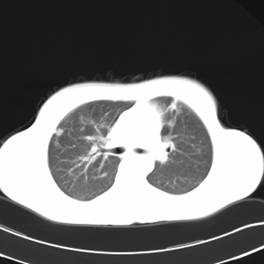

影像学检查:

CT左侧乳腺癌保乳治疗术后,双肺发转移瘤;

右肺中叶炎症;

两个月后患者到医院复查CT发现,双肺发转移瘤明显实现了瘤体萎缩。